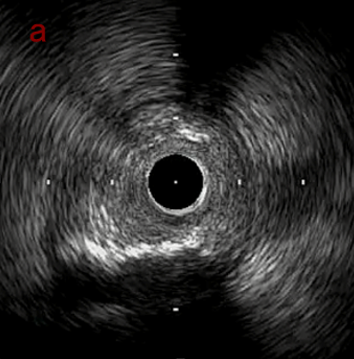

IVUS imaging

IVUSでは8時方向からPD枝がはいいてくる。

PreのIVUSではaの部位のみlipid plaqueを認め削ることでdistal embolismのリスクがあり、そのほかは270度の偏心性石灰化であるがwire biasは良好。